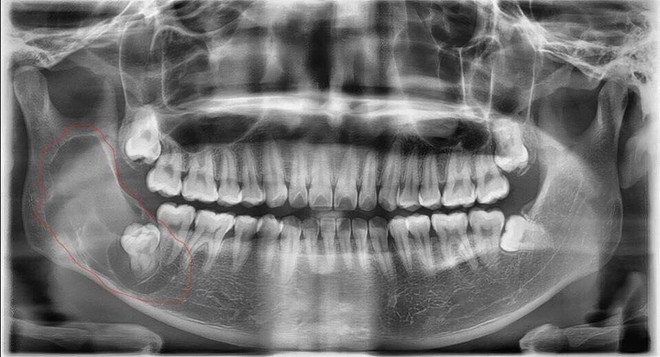

Sau khi chụp Xquang, các bác sỹ thấy khối nang lạ nằm ở vị trí góc hàm kích thước rất lớn, trải dài từ vị trí răng số 7 đi qua cành ngang và cành cao xương hàm dưới, phát triển ra cả hai bản xương trong và ngoài.

Nam thanh niên 26 tuổi có nang răng sừng hóa hiếm gặp ảnh 2Phim chụp nang răng sinh sừng của bệnh nhân. (Ảnh: PV/Vietnam+)